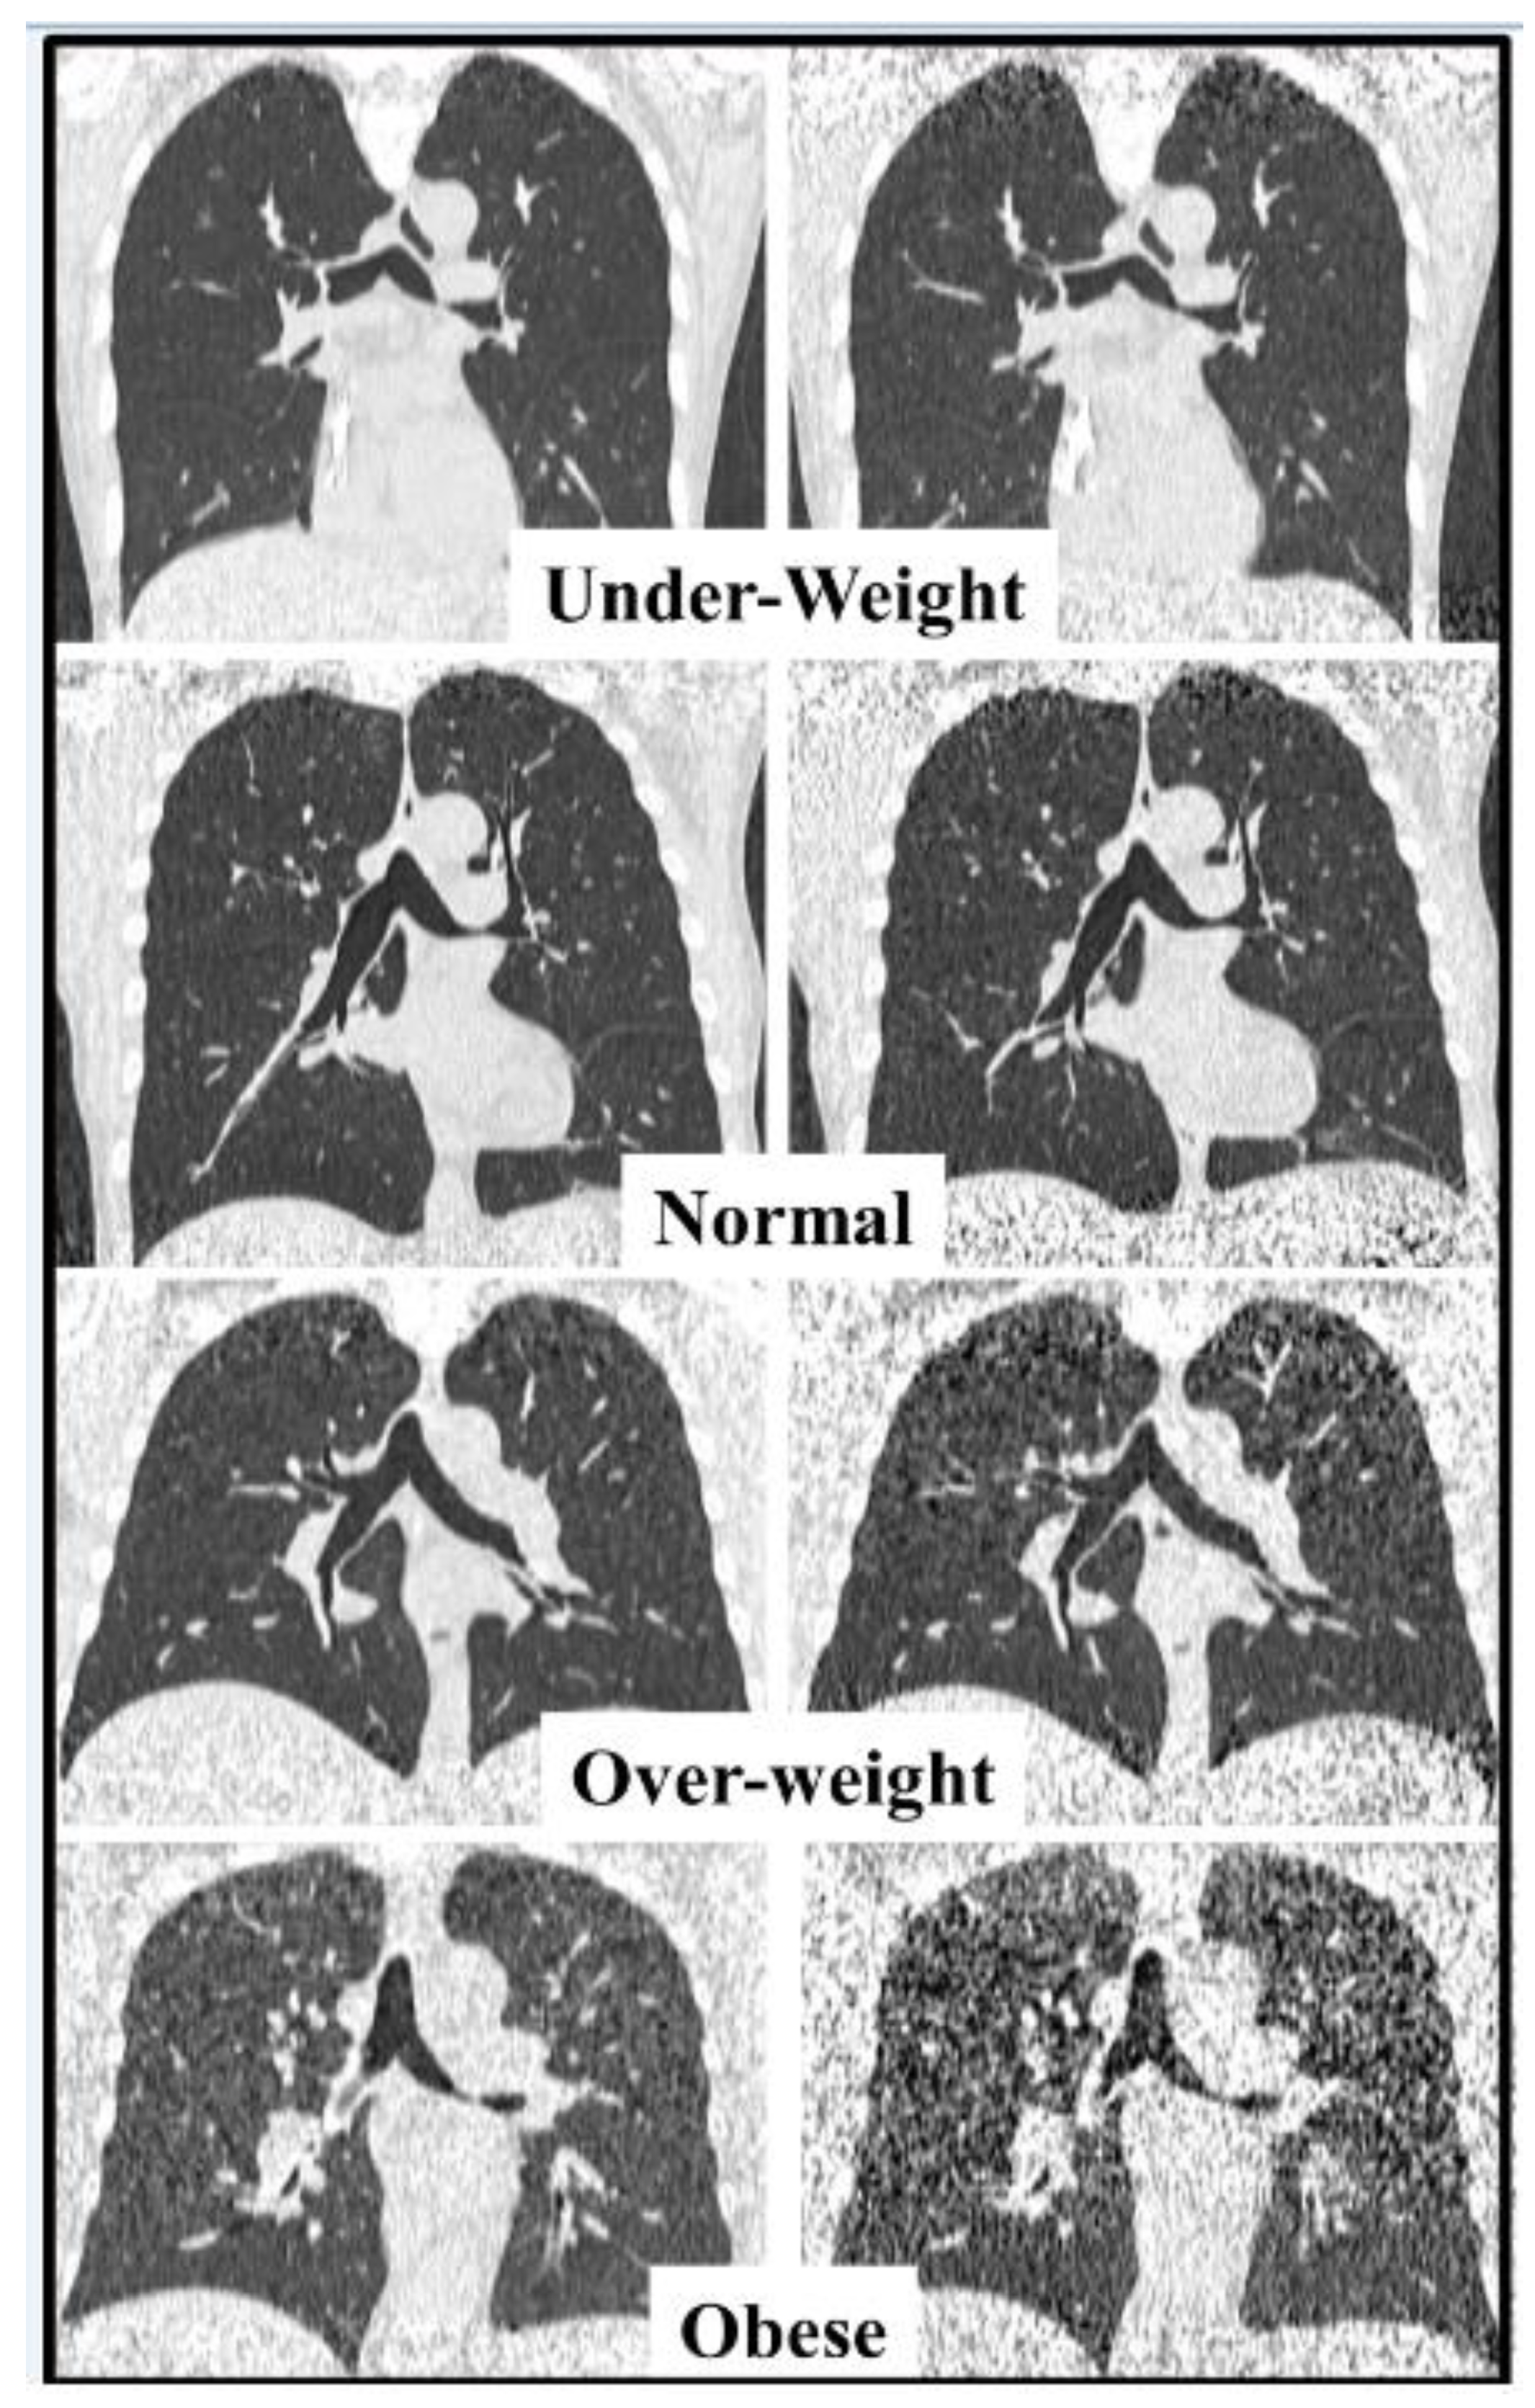

4.1. Image Quality (IQ) Assessment

4.2. Diagnostic Confidence Assessment

5. Discussion